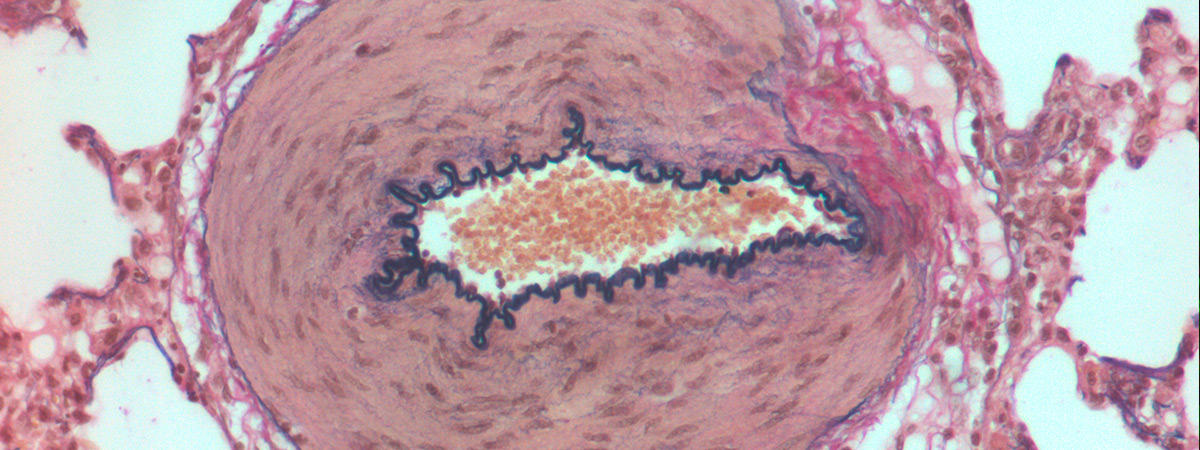

Idiopathic and heritable forms of pulmonary arterial hypertension (PAH) are devastating conditions associated with high morbidity and mortality. The disease is usually diagnosed late by finding a markedly increased pulmonary arterial pressure (increased blood pressure in the arteries of the lungs), the result of progressive narrowing and obliteration of the pulmonary vasculature, which often results in failure of the right ventricle. This disease tends to present in the middle decades of life, with a female predominance.

A major breakthrough in our understanding of the molecular basis of hypertension PAH was the identification of heterozygous germline mutations in the bone morphogenetic protein type II receptor (BMPR-II) in the majority (>70%) of familial cases of the disease and a significant proportion (15-26%) of sporadic cases. Although the presence of mutations in BMPR-II is the greatest risk factor for the development of PAH, it is estimated that only 20% of carriers develop the disease. Additional factors are required for disease manifestation. These may be genetic and/or environmental, though the identity of these factors remains unknown.